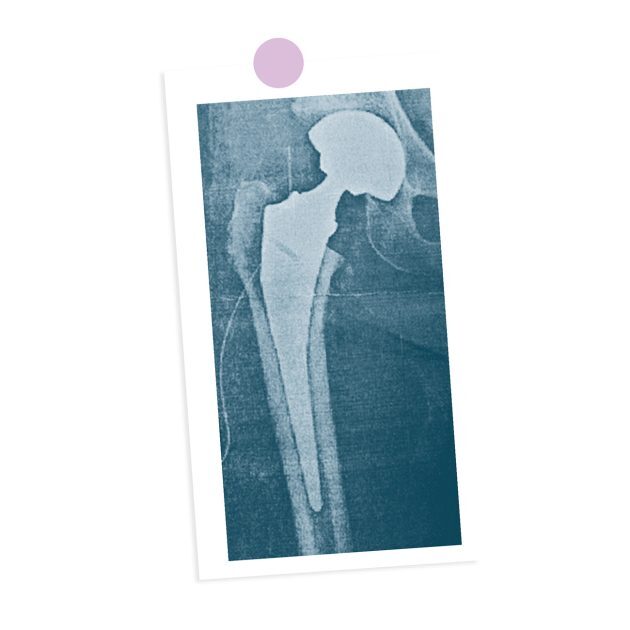

そして、同年8月と12月に、両脚の人工股関節置換術を受けることを決断されたのです。

彼女が受けたのは「人工股関節置換術」という手術で、これは傷んだ股関節を人工の関節に置き換える治療法です。

決して足を切断するようなものではありませんのでご安心ください。

手術によって、長年苦しんだ股関節の痛みはゼロになり、今ではスタスタと快適に歩けるようになったと、ご本人が喜びを語っていらっしゃいます。